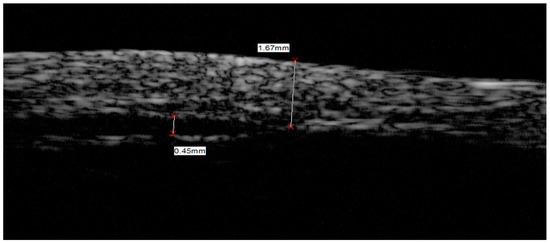

3.3. Ultrasound Bio-Microscope Imaging